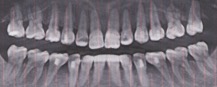

H29.2.

38歳女性

Invisalign failure

矯正したにも関わらず前歯が噛んでいない

インビザライン矯正失敗」というのは、歯列矯正治療の結果が期待どおりにいかなかった場合を指す言葉です。

失敗と感じるケースにはいくつかのパターンがあり、それぞれ原因や対処法が異なります。

インビザライン治療において歯肉退縮が生じることは稀ですが、可能性はゼロではありません。

歯肉退縮は、歯茎が後退し、歯の根元が露出する状態です。これが起こる原因にはいくつか考えられます。

1. 過度な歯の動き: インビザラインによる歯の移動が過剰だった場合、歯茎に負担がかかり退縮することがあります。

2. 歯周病の既往: 既に歯周病のリスクがある場合、治療中に歯肉退縮が進行しやすくなります。

3. 不適切な口腔ケア: 治療中の口腔衛生管理不足も歯肉退縮の原因となることがあります。

4. 個人の解剖学的要因: 歯茎の厚さや骨の構造によっても影響を受けることがあります。

もし歯肉退縮が疑われる場合は、早めに歯科医師または矯正専門医に相談することをお勧めします。

適切な診断と治療計画の見直しが必要です。

場合によっては、歯周治療や歯肉の再生治療が検討されることもあります。